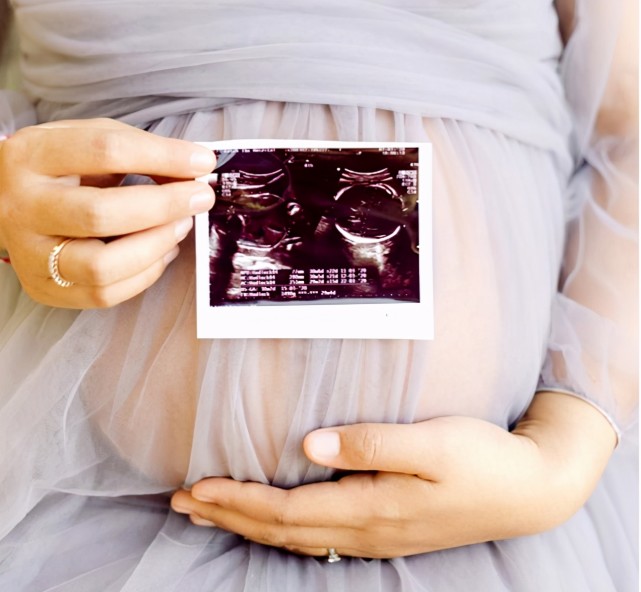

这个孕周段有个重要的产检,叫“排畸B超”。

有的医院是做普通B超进行排畸,有的医院是做四维排畸。

有的医院做一次排畸B超,在孕20-24周做,有的医院做两次排畸B超,孕20-24周做一次,到了孕28周会再做一次。

因为 这1-2次B超都是排查胎儿的重大畸形,准爸爸就更不能缺席了,一定要陪在孕妈身边。

有的医院检查时,准爸爸是可以陪着进去的,那检查时,医生会告诉准爸妈胎儿的各个身体部位,那准爸爸就更不要错过和胎宝宝的第一次见面啦!

普通B超(三维)也完全可以起到排畸的效果,只是四维B超可以算是宝宝的第一张照片,比较有意义;